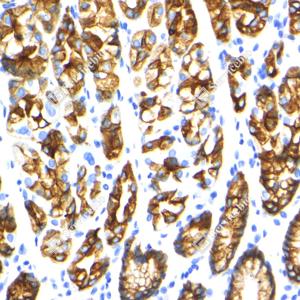

IHC检测Cytokeratin 18蛋白(货号 GB15232). 样品: 人结肠癌, 4%多聚甲醛 (货号G1101) 固定12-24小时. 抗原修复: 柠檬酸抗原修复液(干粉, pH 6.0) (G1201), 高压锅均匀喷气计时2分钟. —抗: 1: 500稀释, 4℃ 孵育过夜. 二抗: S-vision免疫组化多聚二抗(山羊抗小鼠), 即用型(货号G1301), 室温孵育20分钟. |